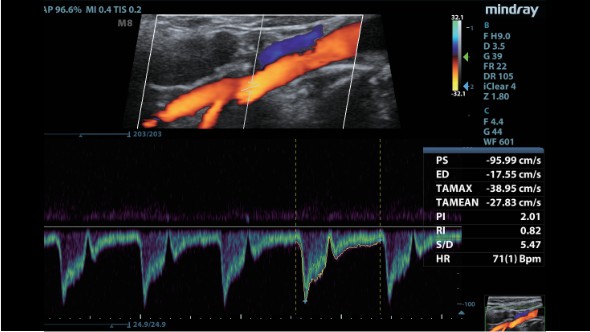

Клинические изображения